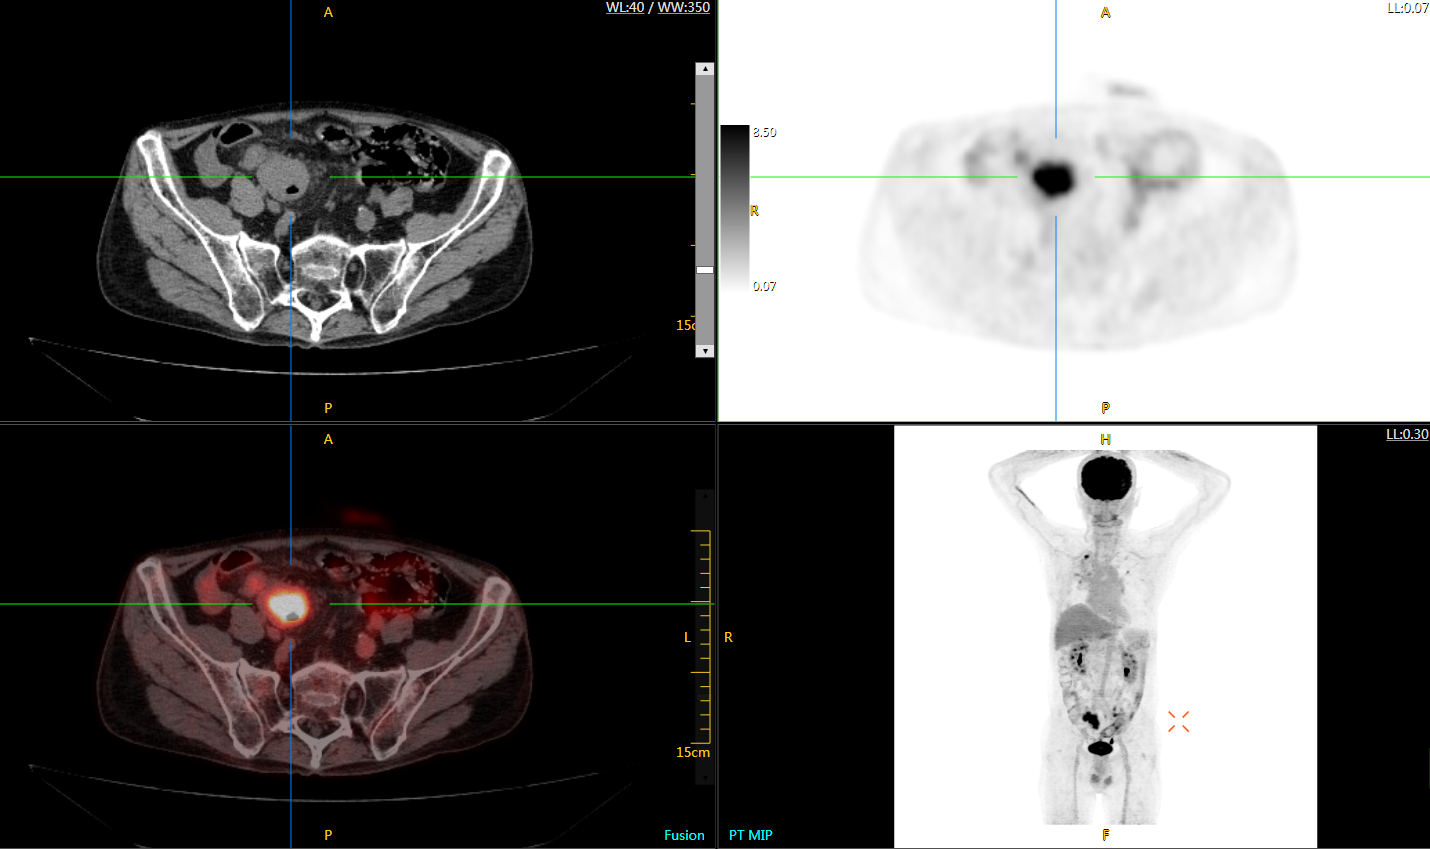

肺癌轉(zhuǎn)移及復(fù)發(fā)

患者男性,66歲,七年前發(fā)現(xiàn)右肺肺癌,其間手術(shù)兩次,共切除兩個(gè)肺葉,復(fù)查;

診斷意見(jiàn),回腸轉(zhuǎn)移,右肺殘留部復(fù)發(fā)